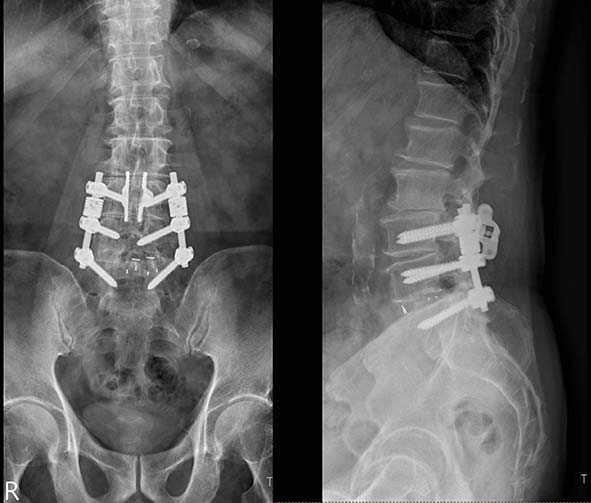

朱晟瑋表示,腰椎無鋼釘穩定器微創術先移除阻礙腰椎活動鋼釘及脊突間金屬融合器,接續施作顯微神經減壓術,搭配骨塊與支架穩定器術加固腰椎及擴大神經椎間孔空間,消除坐骨神經壓力。

朱晟瑋表示,傳統腰椎鋼釘固定術可能誤傷神經,造成下肢麻痺無力、跛腳甚至排泄異常,術後衍生背痛、加速椎間退化等後遺症,嚴重須多次開刀治療。圖/七賢脊椎外科醫院提供、文/高培德